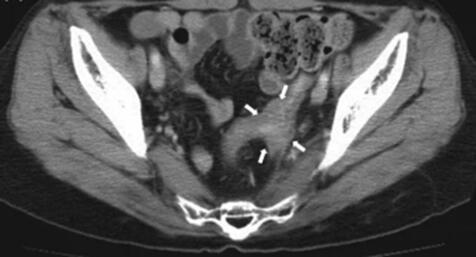

陈女士说,相比其他中晚期患者,她已经幸运很多了。起码是早期发现,生存希望还很大。在确认病理结果后,陈女士迅速和主治医生敲定了手术方案。手术很顺利地切除了癌变卵巢,保留子宫和对侧卵巢,且术后CT复查也显示她的体内已经没有任何病灶了。

我的的治疗团队细致地为她制定了个性化的治疗方案。陈女士开始接受每2周1次的NKT细胞治疗。12月9日,陈女士第一次接受NKT细胞治疗时淋巴细胞百分比是14%,但在12月22日接受第2次NKT细胞治疗后,淋巴细胞百分比上升至22%,接受第4次NKT细胞治疗后,数值已上升至至35%。